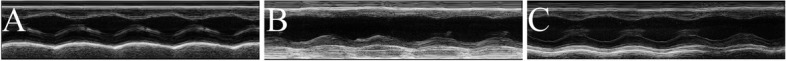

The results of LV cardiac remodeling in LV end-diastolic dimension (LVIDd), LV end-systolic dimension (LVIDs), were revealled in Fig. 1 and Table 1.

Fig. 1.

Typical transthoracic echocardiography images from effects of HA + GA on CHF rats. HA: hypaconitine; GA: glycyrrhetinic acid. Sham group (A), Model group (B), and HA + GA group (C)

Comparing with the Sham group, the values of LVIDd (P < 0.01) and LVIDs (P < 0.05) were both increased in the Model group. At the same time, when the HA + GA group compared to the Model group, the values of LVIDd (P < 0.01) and LVIDs (P < 0.05) were both descended. This results indicated that the LV cardiac remodeling of CHF were obviously ameliorated by the HA + GA treatment.